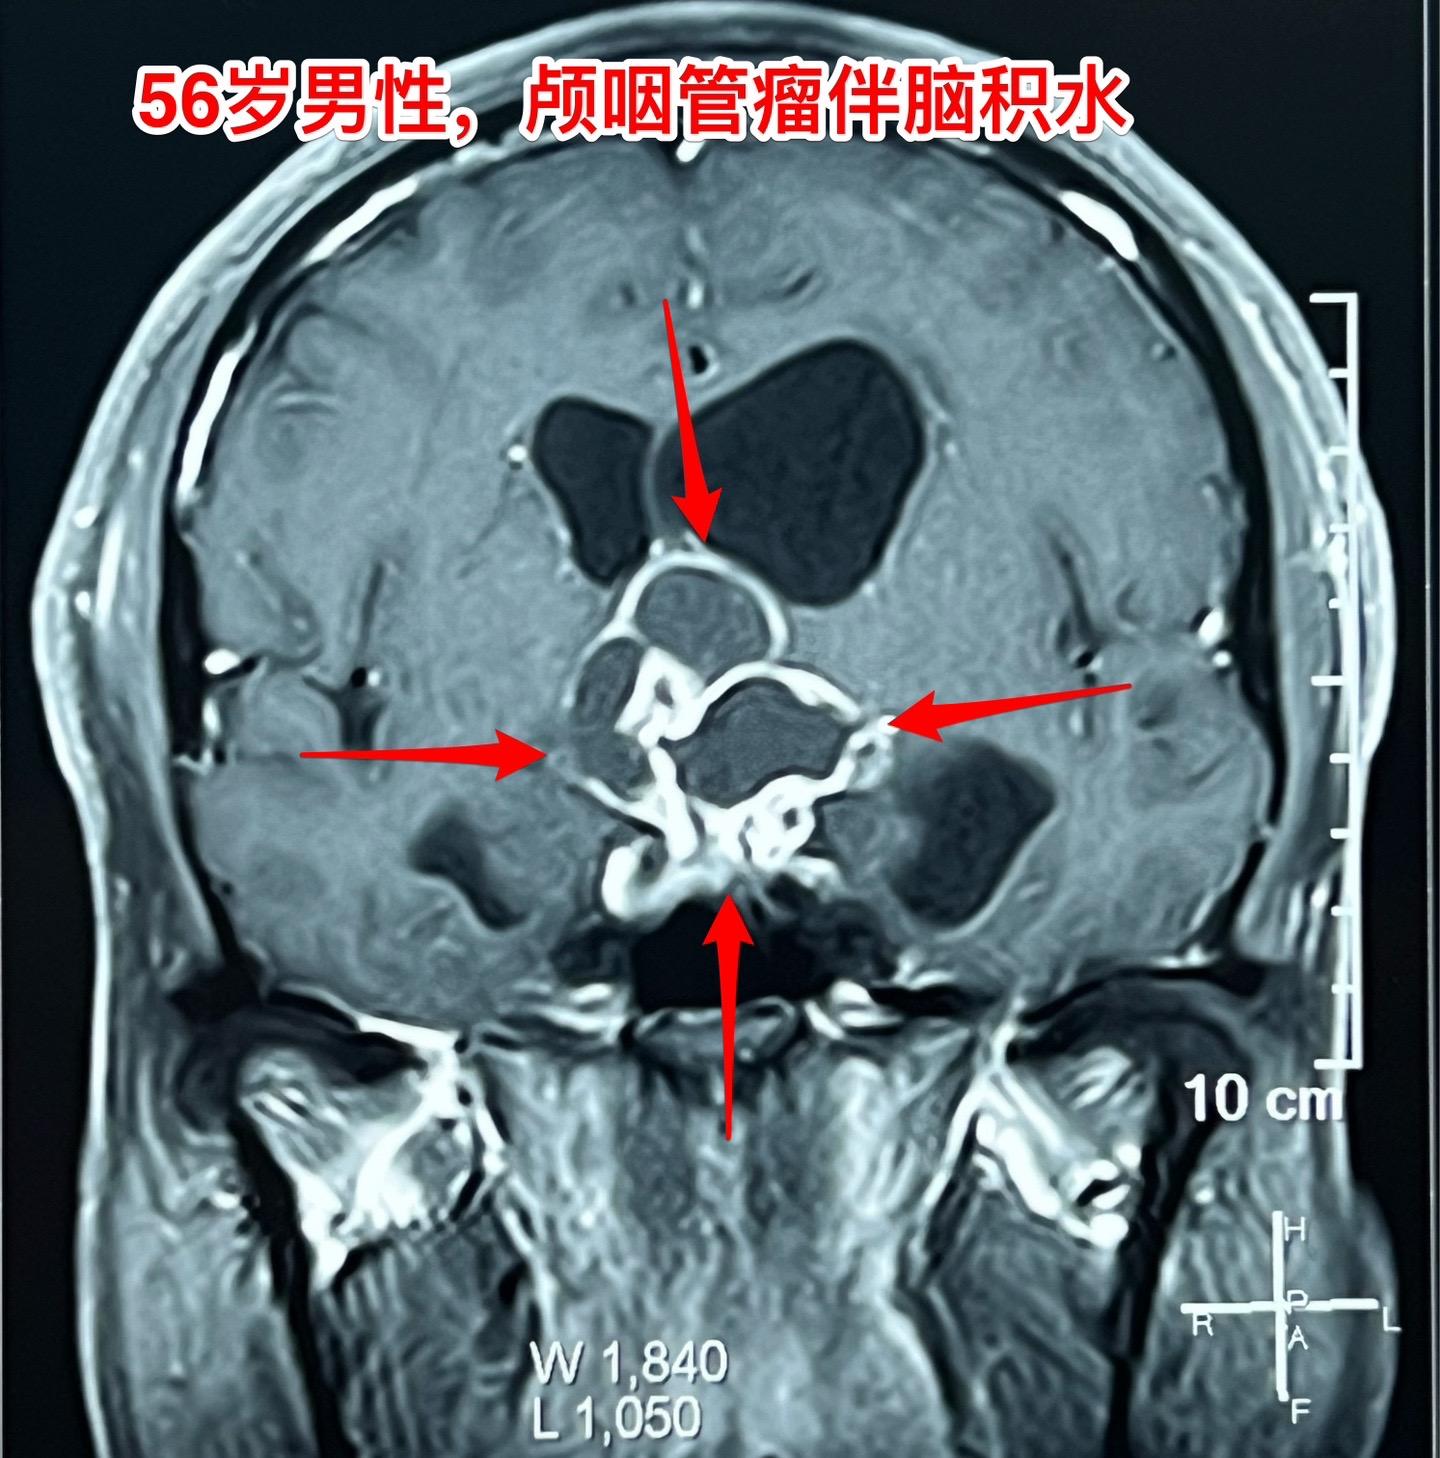

一天两个颅咽管瘤手术,凌晨两点才到家 科里年轻医生说还在关颅。 第一个病人广州人,56岁,左眼视力下降,检查出颅咽管瘤已经半年了,近期出现记忆力下降。病人之前一直在赶在过年前来作手术。今天的手术很顺利。 第二个病人是40岁大同市男性,思维糊涂、精神萎靡,坐轮椅到三博脑科医院就诊,颅咽管瘤伴有脑积水。今天的手术也是很顺利。